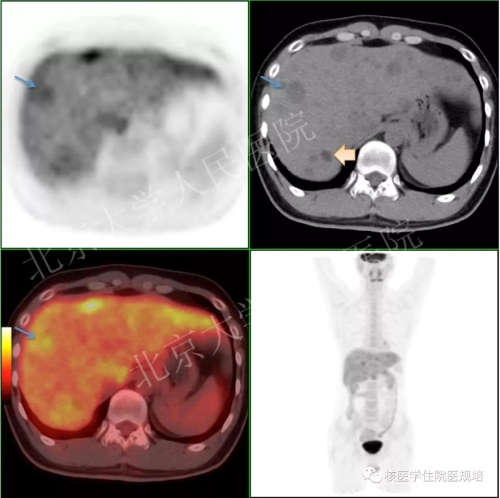

图3. 18F-FDG PET/CT图:病灶1(蓝色箭头)CT值较高(约30HU),呈FDG摄取增高表现;病灶2(黄色箭头)CT值较低(-8HU),未见明显FDG摄取增高表现。

18F-FDG PET/CT见肝脏大小、形态可,内见多发大小不等类圆形低密度结节影(CT值分布在-10~30HU),直径分布在0.7-3.5cm,结节边界清晰,其内呈不同程度FDG摄取(SUVmax:2.8-4.6,肝实质SUVmax:2.8),且结节密度与其FDG摄取程度相关(CT值较高者FDG摄取相对较高);肝内、外胆管未见增宽。扫描野内其它部位未见明显异常结构改变或FDG摄取。

肝脏多发FDG代谢增高结节,结合病史及MRI考虑良性病变可能性大(肝多发性局灶性脂肪变性?),需与其他恶性肿瘤(如脂肪肉瘤、转移瘤等)鉴别,建议进一步组织病理学检查。